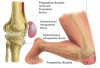

무릎 점액낭은 무릎의 피부와 뼈돌출부 사이 또는 힘줄/인대/뼈 사이에 위치한 주머니 구조물입니다.

임상적으로 suprapatella, prepatella, infrapatellar, pes anserinus bursa 등이 주로 문제가 됩니다.

분류

- 상슬개점액낭염(suprapatella bursitis)

- 전슬개점액낭염(prepatella bursitis, housemaid knee)

- 하슬개점액낭염(infrapatellar bursitis, clergyman’s knee)

- 거위발점액낭염(pes anserinus bursitis)